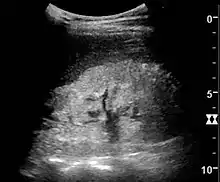

Further investigations are indicated if the cause is not clear including analysis of auto-immune markers (ANA, ASOT, C3, cryoglobulins, serum electrophoresis), or ultrasound of the whole abdomen.